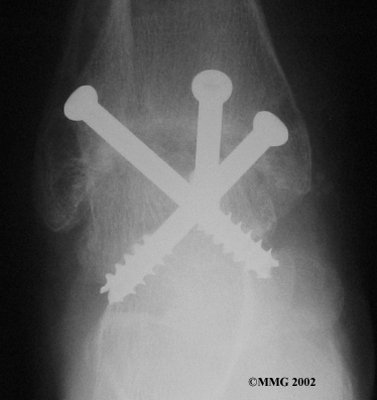

It is important when the surfaces are removed that the angles of the cut surfaces are correct. When the tibia is brought against the talus, the foot should be at a right angle to the lower leg. Once the cuts are made the bones must be held in place while they fuse. This can be done using large metal screws and metal plates if necessary. The screws are usually under the skin and are not removed unless they begin to rub and cause pain.

Inserting the screws

After ankle fusion, the physical therapists at FYZICAL Uxbridge can help you learn to walk smoothly and without a limp. Although time needed for recovery varies among patients, an ankle brace will typically replace your cast after eight to 12 weeks. Your surgeon will take X-rays frequently to see if the bones are fusing together. You will probably need to use crutches during the time you wear the cast. As the fusion grows stronger, you will begin to put more weight on your foot when walking.